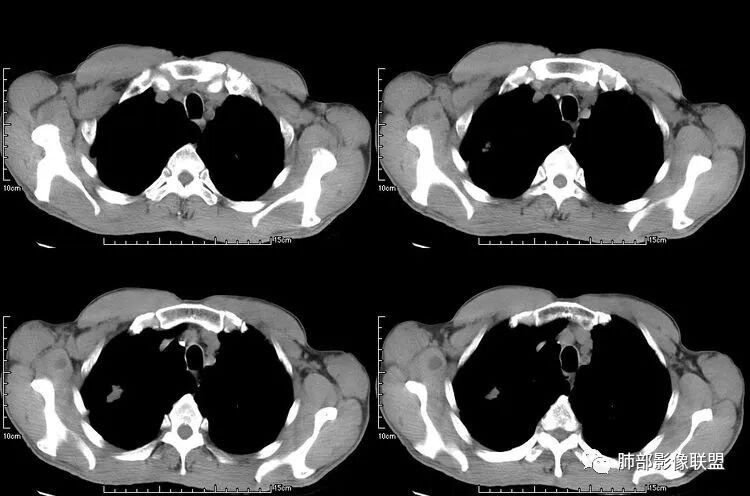

患者老年男性,咳嗽、咳痰、痰中带血伴胸闷2月余。长期大量吸烟史。查肝肾功能、血糖、血脂、心肌酶、电解质、血沉、C反应蛋白、抗“O”、类风湿因子、抗核抗体谱无明显异常。肿瘤标志物提示NSE、CYFRA21-1稍升高。胸部CT:肺气肿背景,左肺下叶后基底段不规则肿块影,见支气管截断,内见大片状低密度区及部分血管影,增强轻度强化,远端空洞形成。双肺多发不规则实性结节影、见毛刺、胸膜牵拉及血管集束,结节内见空洞形成,部分可见血管影,多位于胸膜下。双肺见多发肺大泡。综合考虑左下肺恶性病变并双肺转移。鳞癌或淋巴瘤可能。鉴别血管炎性病变及真菌感染。

肺是发生转移瘤最多的脏器,几乎所有恶性肿瘤都可转移到肺,血行转移是最重要的转移途径。典型的肺转移瘤表现为多发圆形、大小不一的实性结节,边缘一般光整,多位于肺周边,多能明确诊断。空洞型肺转移瘤相对少见,约占肺转移瘤4%,其中70%为鳞癌转移;常见的空洞型肺转移瘤的原发恶性肿瘤多见于头颈部的鳞状上皮癌、胃肠道的腺癌和女性的生殖系统肿瘤以及其他部位的肉瘤等,组织学以鳞癌和腺癌最多见。

本病例左肺下叶肿块,有深分叶、毛刺、胸膜牵拉凹陷、支气管截断及纵隔内淋巴结肿大等征象,都均支持病灶为恶性,如腺癌,而且叶间裂的多发结节也提示是腺癌来源可能大;双肺多发结节、肿块,大部分病灶有分叶、毛刺及胸膜凹陷的恶性征象,与原发肿瘤本身的性质有关,所以应该与左肺下叶肿块同源,而且双肺多发病灶内空洞也具有多样性;